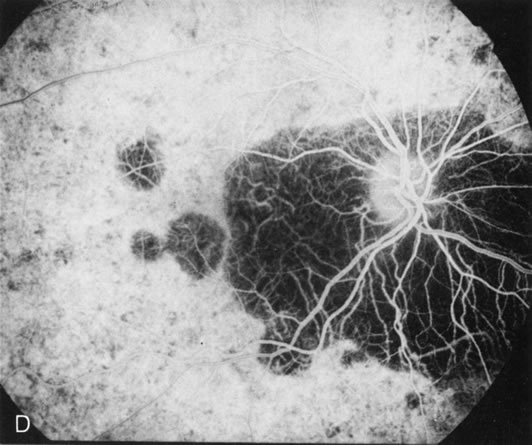

Of more clinical importance is the role of FA in the diagnosis and treatment of cystoid macular edema (CME) (Fig. 1C and D). Stereoscopic FA indicates that the leakage, which may be diffuse or have the typical petaloid stellate appearance of CME, can come from the perifoveal retinal capillaries, from the choroid through the RPE, or from a combination of both sources.4 With the recent suggestion that CME in RP may be successfully treated with acetazolamide,5, 6 FA is thus important to document the diagnosis of CME, establish the origin(s) of leakage, and follow patients during and after therapy.